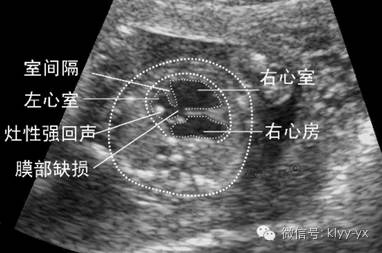

胎儿畸形种类繁多,从大范围来说,胎儿畸形包括染色体畸形和形态畸形两方面,而只有形态畸形才是超声的检查范围,但是某些染色体畸形伴随形态畸形也在超声诊断范围内。

我国卫生部重点强调了致死性胎儿畸形的超声检查,包括无脑儿、明显的脑膨出、明显的脊柱裂、胸腹壁缺损、内脏膨出、致死性的软骨畸形等,只有这几种是医生应该能诊断出来的。其他一些畸形可能会诊断出来,但不是所有的医院都能确诊。